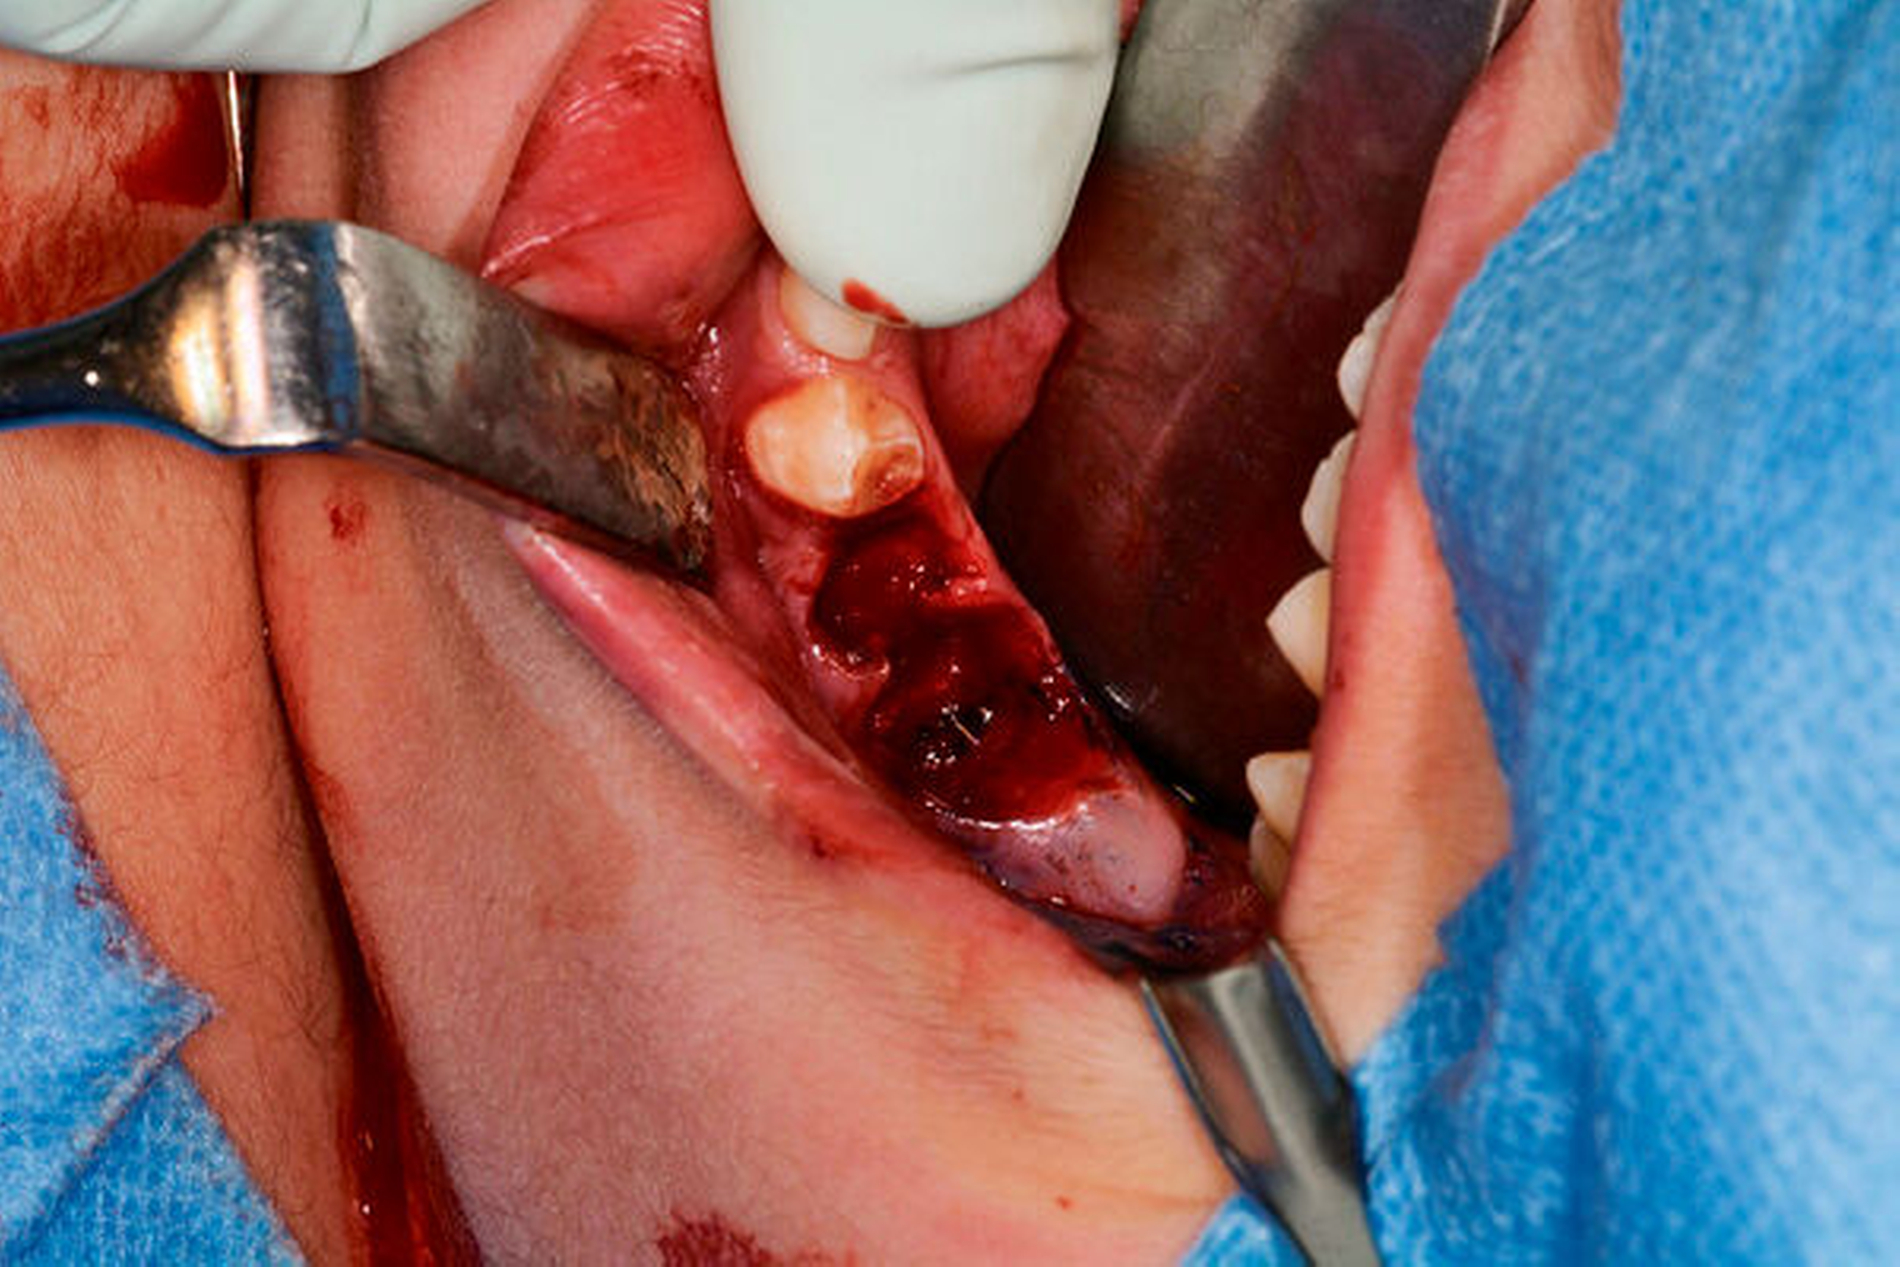

Therapeutisch wurde die Extraktion der Zähne 75 und 36 sowie die Fistelexzision mit Narbenkorrektur von extraoral in Vollnarkose durchgeführt. Hierzu wurde der Fistelgang zunächst sondiert und mit Methylenblau markiert (Abbildungen 3 und 4). Aus der Extraktionsalveole in Regio 36 trat das Färbemittel in die Mundhöhle über (Abbildung 5). Unter Umschneidung des Narbenkeloids wurde die Fistel mit lingualer Anheftung am Periost freipräpariert und in toto reseziert (Abbildungen 6 bis 8). Die histopathologische Aufarbeitung des entnommenen Resektats ergab eine chronisch-floride, granulierende Entzündung mit Fistelgang, passend zum klinischen Befund einer Partsch-Fistel.